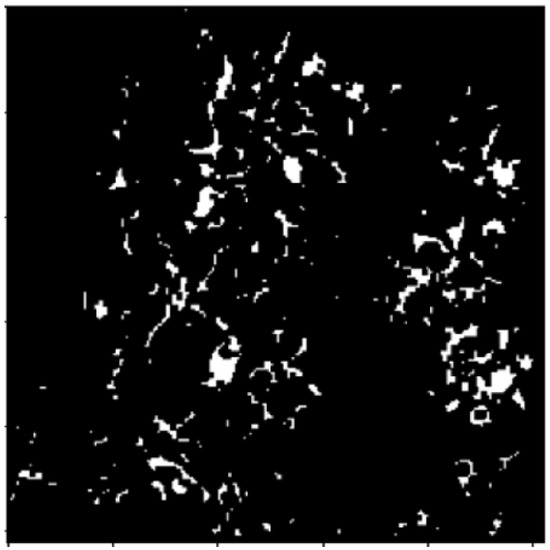

2.2.1. Thresholding

2.2.2. Morphology Operations